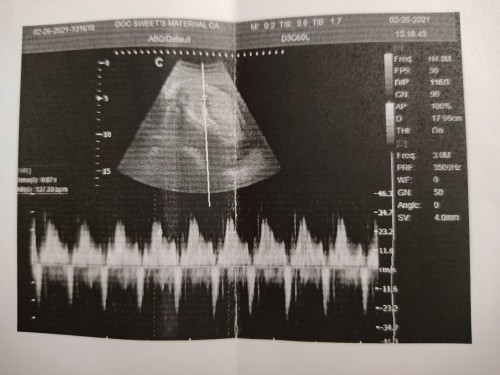

Monthly po ako nagpapa check up since nalaman kong preggy ako sa first baby ko unang OB na tumitingin sa amin ni baby hanggang 4mos wala naman syang nasabi na problema pero binibigyan parin nya ako ng meds pampakapit ni baby every visit ko sa kasi nag aalala ako lagi ko sinasabi na madalas sumakit ang tyan ko and nag undergo din ako urinalysis test at nalaman kong may UTI ko, sinabi narin ni OB gender ni bby hindi ako makapaniwala na ganun kaaga ko malalaman ang gender nya but then nung 6mos si baby nagpasya ako lumipat ng OB kasi medyo hindi ako nasasatisfy sa OB ko every visit ko. I remember nung check up ko maaga ako pumunta ng clinic nauna pa ako sa OB sabi ng midwives nya balik nalang daw ako hapon nung pauwi na ako nasa exit door palang ako bigla ako nahilo then nagsuka kaya ako priority nila pinag laboratory test uli ako pero bumaba ang UTI ko, normal naman yung ibang tests pero ang pinagtataka ko SOBRANG NANINIGAS ANG TYAN KO HABANG INUULTRA SOUND NADUDULAS PA YUNG HAWAK NI DOC MATIGAS DAW TALAGA TYAN KO, MATAGAL NYA CHINECK ANG TYAN KO OKAY NAMAN DAW SI BABY PERO YUNG PLACENTA KO NASA BABA DAW NASA CERVIX KO NA BANDA TINANONG NYA KO NG PAULIT ULIT KUNG NAG BLEEDING BA AKO SABI KO NEVER AKO NAKA EXPERIENCE NG BLEEDING PERO NAALALA KO BIGLA NASA 2MOS PALANG SIGURO NAG SPOTTING PALA AKO HINDI KO PA ALAM NA BUNTIS AKO NUN, NABAHALA AKO KASI SABI NI OB WHENEVER MAG BLEEDING DAW AKO TAKBO AGAD AKO SA OSPITAL OR SA CLINIC NYA AT MAY TENDENCY DAW NA MA CS AKO. NAGPA ULTRASOUND AKO ULIT AFTER 2WEEKS NASA CERVIX KO PARIN DAW ANG PLACENTA PERO HINDI NAMAN AKO NAG BLEEDING UNTIL NOW. ANO KAYA ANG POSSIBLE REASON AT NAPUNTA ANG PLACENTA SA CERVIX KO? #pregnancy #firstbaby #advicepls #pleasehelp